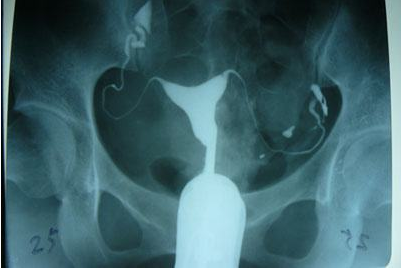

輸卵管造影是用來檢查女性輸卵管通暢與否的一種檢測方法。目前,輸卵管造影是臨床上應用較為廣泛的方法之一。造影是通過導管經陰道、宮頸、子宮腔直接插向子宮角的輸卵管開口處,對著輸卵管推注造影劑而使輸卵管顯影,進而了解輸卵管是否通暢、阻塞部位及宮腔形態的一種檢查方法。

輸卵管造影檢查可直觀了解輸卵管是否通暢以及阻塞的部位,觀察子宮腔的大小、形態、有無畸形及有無宮腔粘連或占位性病變,而且不孕不育專科醫院所采用的造影劑都是對人體沒有傷害可吸收的,對輕微的輸卵管堵塞患者還能疏通治療,可以在次月實施備孕。

推注造影劑力,造影劑進入盆腔緩慢,在停注造影劑數十分鐘后,可見造影劑在盆腔內彌散,但彌散欠佳。

2. 輸卵管不通

輸卵管完全不顯影或顯影一段后不再顯影,且造影劑注入到一定劑量時阻力加大,盆腔內無造影劑影彌散。

3. 輸卵管積水

造影劑積聚在輸卵管內,輸卵管常擴張呈囊狀或臘腸狀,以遠端明顯,多伴有輸卵管傘端阻塞。盆腔內一般無造影劑影彌散。